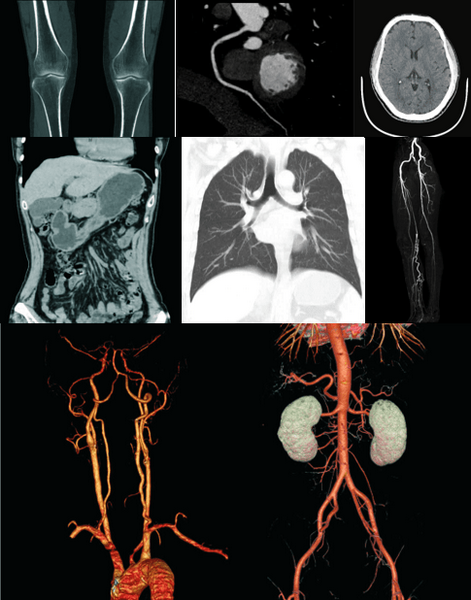

• Clinical Applications. Fast, precise and low-dose imaging provide a full range of clinical solutions to meet the current and future clinical diagnostic needs of the hospital.

AccuOrgan-High resolution lung imaging.

High resolution images of the lung are obtained only by using 30 % – 40% of conventional radiation dose.

AccuBone-High resolution bone imaging.

Enhanced lesions edge contrast can provide accurate anatomic relationships and show early destruction and cyst of subchondral bone like lesions and articular cartilage calcifications.

AccuOrgan-Body high resolution imaging.

Combined with the AccuImage microscopic imaging technology, significantly to increase the display of fine structure and morphology of the abdomen and provide more accurate images for the early diagnosis of small lesions.

AccuImage-Microscopic imaging technology.

1024 x 1024 matrix to display more details of the pathological changes and provide a reliable basis for early detection & diagnosis and early treatment of the diseases.